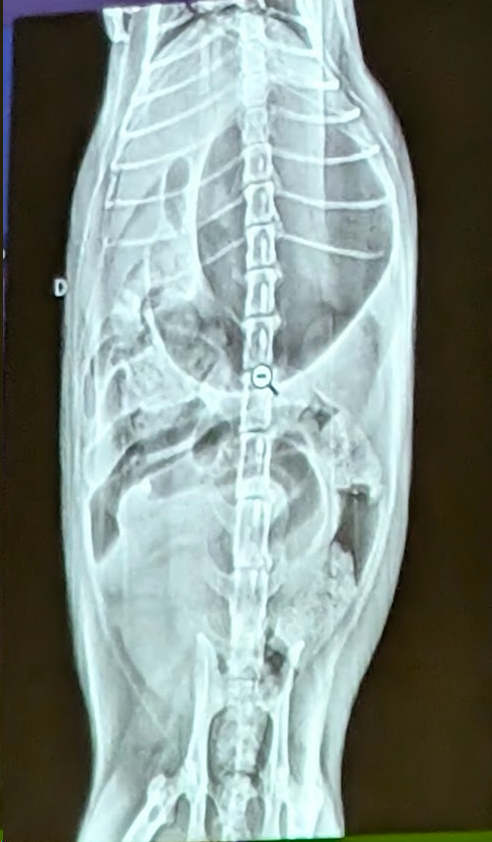

- Se trata de un abdomen de gato

- Obstrucción intestinal

- Presenta una dilatación gastrica sin torsión (ya que el fundus y piloro gastrico están en su sitio).